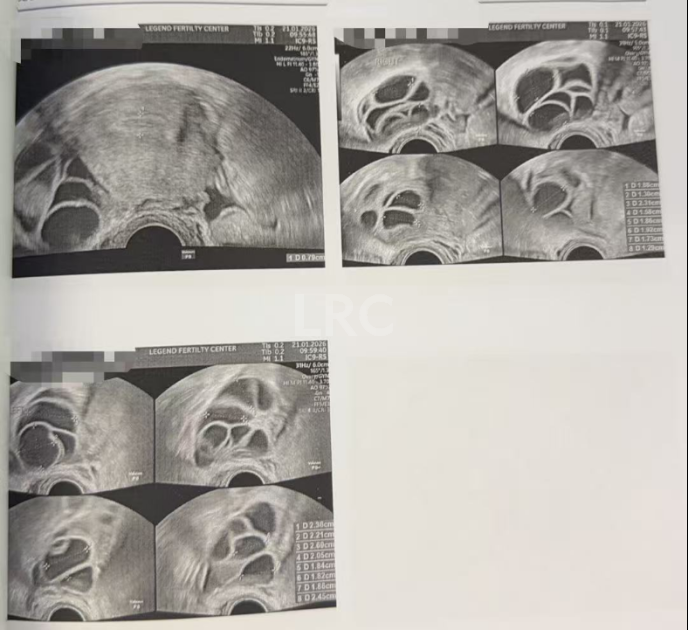

月经第二天 促排第一天

阴超检查:基础卵泡 16 颗

- 右侧卵泡 8 颗 (8,6,5,5,5,4,4,4mm)

- 左侧卵泡 8 颗 (6,6,6,5,5,5,5mm)

促排第四天

阴超检查(只数能用卵子):

- 右侧卵泡 8 颗 (10,9,9,8,7,7,7mm)

- 左侧卵泡 8 颗 (12,11,10,9,9,9,8,8mm)

子宫内膜厚度:6.4mm

促排第六天

阴超检查:

- 右侧卵泡 9 颗 (12,10,9,9,9,8,8,7,7mm)

- 左侧卵泡 9 颗 (13,11,11,11,10,10,9,6,6mm)

子宫内膜厚度:5.5mm

促排第九天

- 右侧卵泡 9 颗 (17,17,16,16,15,15,13,12,12mm)

- 左侧卵泡 10 颗 (19,17,16,16,15,15,14,14,13,12mm)

子宫内膜厚度:7.0mm

促排第十天

- 右侧卵泡 9 颗 (20,18,18,18,18,17,17,15,14mm)

- 左侧卵泡 10 颗 (21,20,20,20,20,18,17,13,12,12mm)

子宫内膜厚度:7.9mm